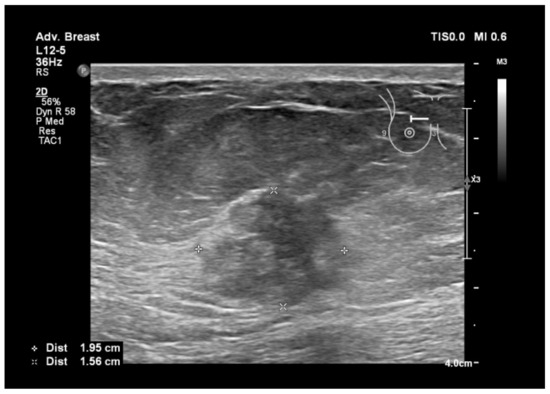

6.1. Characterization of Lesions

9. Types of Lesions Found by Screening with Breast Ultrasound